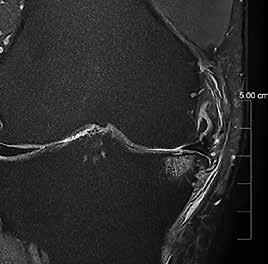

Ziel der Forschungen an der Universität Bordeaux war die hochaufgelöste und detailreiche Darstellung spezieller Hirnareale, wie des Hippocampus oder des Claustrum. Diese Regionen hatte Prof. Tourdias schon am 7T-System bei seinem Aufenthalt an der Stanford-Universität studiert. Nun war es mit der AiCE-Technologie möglich, vergleichbar aufgelöste Bilder auch bei 3T in akzeptabler Untersuchungszeit zu erzeugen (siehe Abb. 5 a und b).

Natürlich lassen sich die Vorteile einer höheren Auflösung nicht nur in der klinischen Forschung nutzen, sondern sind auch dazu geeignet, bei-

Abb. 5 a + b: Hochaufgelöstes Bild des Hippocampus; 0,15 mm x 0,15 mm; 2 mm Schichtdicke; rechts mit AiCE-Rekonstruktion. Mit freundlicher Genehmigung des Unversitätsklinikums Bordeaux. Abb. 6 a + b: Hochaufgelöstes Bild des Knies; 0,15 mm x 0,15 mm (interpoliert); 1 mm Schichtdicke; rechts mit AiCE-Rekonstruktion.

42 // VISIONS 31

spielsweise einen Knorpelschaden im Knie im Detail zu zeigen.